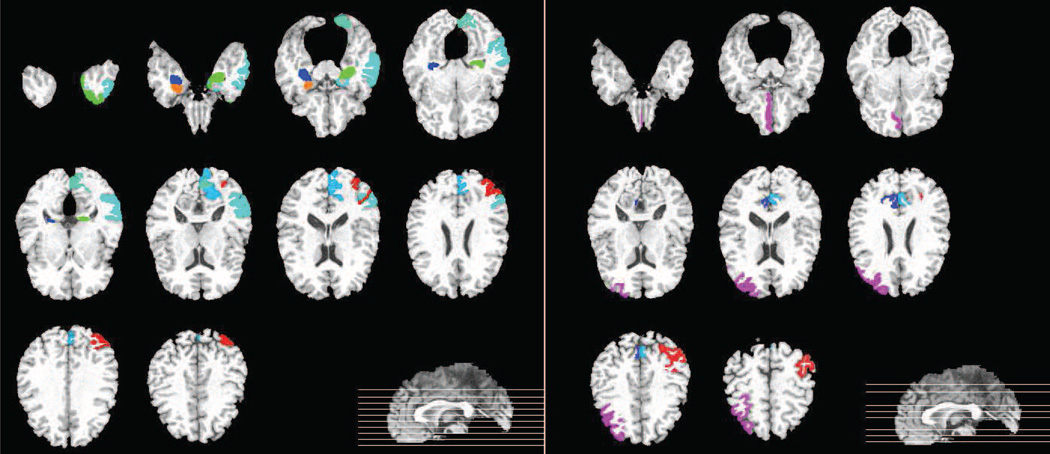

4.6. Most discriminative features

In addition, we also include the distribution of the most discriminative features according to modalities in Table 9. We define the most discriminative features (MDFs) as the features that were selected for more than 90% of the times, i.e., more than 90 times in the 10 repetitions of the 10-fold cross-validation run. Most of the MDFs are located in MRI modality, for both the AD/NC and MCI/NC classifications. We also observed that more features were selected for AD/NC than MCI/NC classification. This is probably because MCI, which is the early stage of AD, affects less brain regions (or ROIs) if compared with AD, where its abnormalities are widely spread across brain regions.

Table 10 shows the names of the MDFs for each modality. The common MDFs selected for AD/NC and MCI/NC classifications are also included in Table 10, if exist. The common MDFs for MRI modality include hippocampal formation, middle temporal gyrus, uncus, and amygdala. The atrophy at these ROIs has been reported to be associated with memory and cognitive impairments or closely related to the AD/MCI pathology (De Leon et al., 1997; Convit et al., 2000; Yang et al., 2012; Poulin et al., 2011). For AD/NC classification, since there are many MDFs from MRI, we only list the MDFs that were selected in all cross-validations and repetitions in Table 10.

On the other hand, the common MDFs for FDG-PET modality include middle frontal gyrus and precuneus, which are similar to the findings in (Mielke et al., 1998; Scarmeas et al., 2004). For CSF biomarkers, the selected MDFs were t-tau/Aβ42 for AD/NC classification and Aβ42 and t-tau for MCI/NC classification.

Figures 6 and 7 graphically show the locations of the selected ROI-based features (for MRI and PET modalities) for both the AD/NC and MCI/NC classifications, respectively.

Figure 6.

MDFs in AD/NC classification. (Left: MRI, right: PET)

Figure 7.

MDFs in MCI/NC classification. (Left: MRI, right: PET)